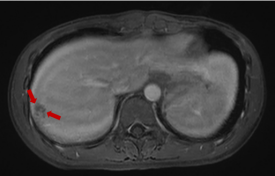

磁共振显示:肝右叶包膜下见多处团片状、楔形病灶,大者位于S7段,范围约2.7cm×1.8cm,部分病灶内见门静脉穿行,门脉血管无阻塞或异常征象,边界欠清。提示:肝右叶包膜下多发异常信号。